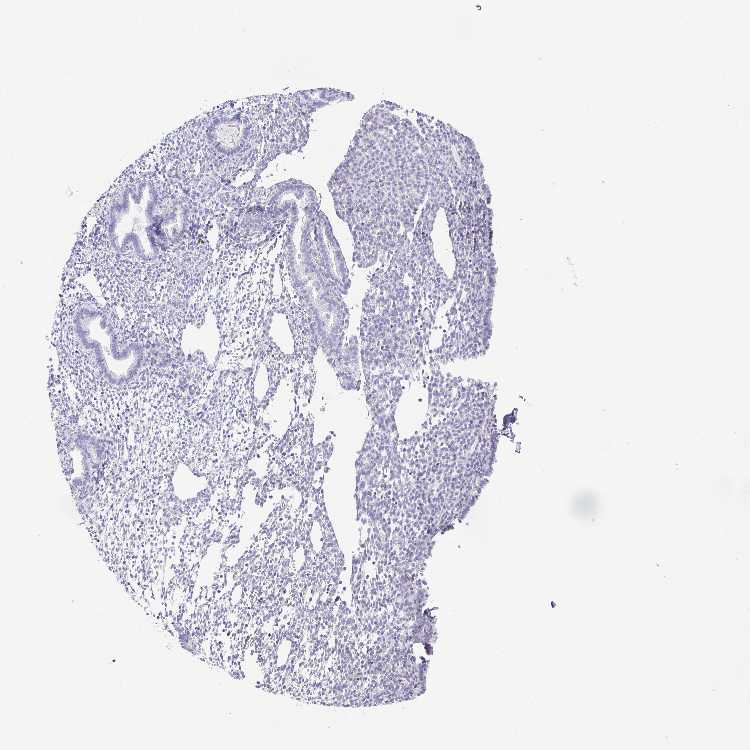

ENDOMETRIUM 1 - Antibody stainingi

Antibody staining in the annotated cell types in the current human tissue is reported as not detected, low, medium, or high, based on conventional immunohistochemistry profiling in selected tissues. This score is based on the combination of the staining intensity and fraction of stained cells.

Each image is clickable and will lead to virtual microscopy that enables deeper exploration of all samples and also displays staining intensity scores, fraction scores and subcellular localization as well as patient and tissue information for each sample.

Antibody HPA039314Antibody HPA039742

Cells in endometrial stroma Not detectedNot detected

Glandular cells Not detectedNot detected

ENDOMETRIUM 2 - Antibody stainingi

Cells in endometrial stroma Not detectedLow

Glandular cells Not detectedLow